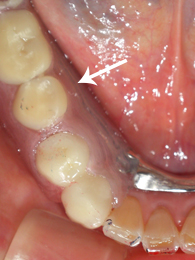

60代 女性 右下567 香芝市

〔術後〕

ぴったりと装着出来ています。今のところ快適です。ありがとうございます。